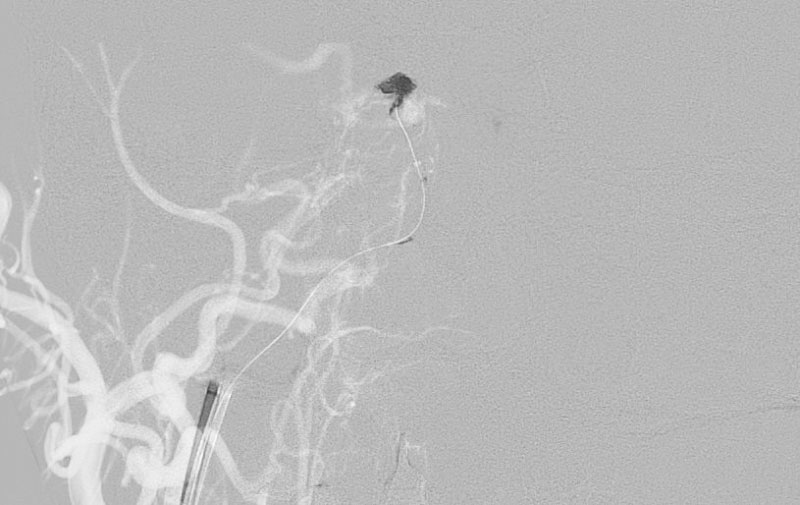

1236

'22年6月14日

右側海綿静脈洞部硬膜動静脈瘻

50代

大阪府の病院

手術写真

治療

前

中

後